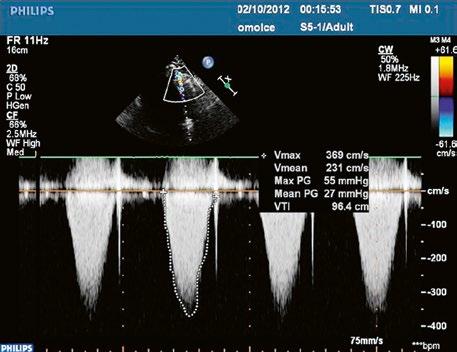

Obr. 45.23 Dopplerovský záznam mitrálního průtoku z TEE u pacienta po uzávěru inkompletního AVSD a plastice mitrální chlopně v dětství s reziduální kombinovanou mitrální vadou, mitrální stenózou a regurgitací ( Video 45.19, Video 45.20, Video 45.21)